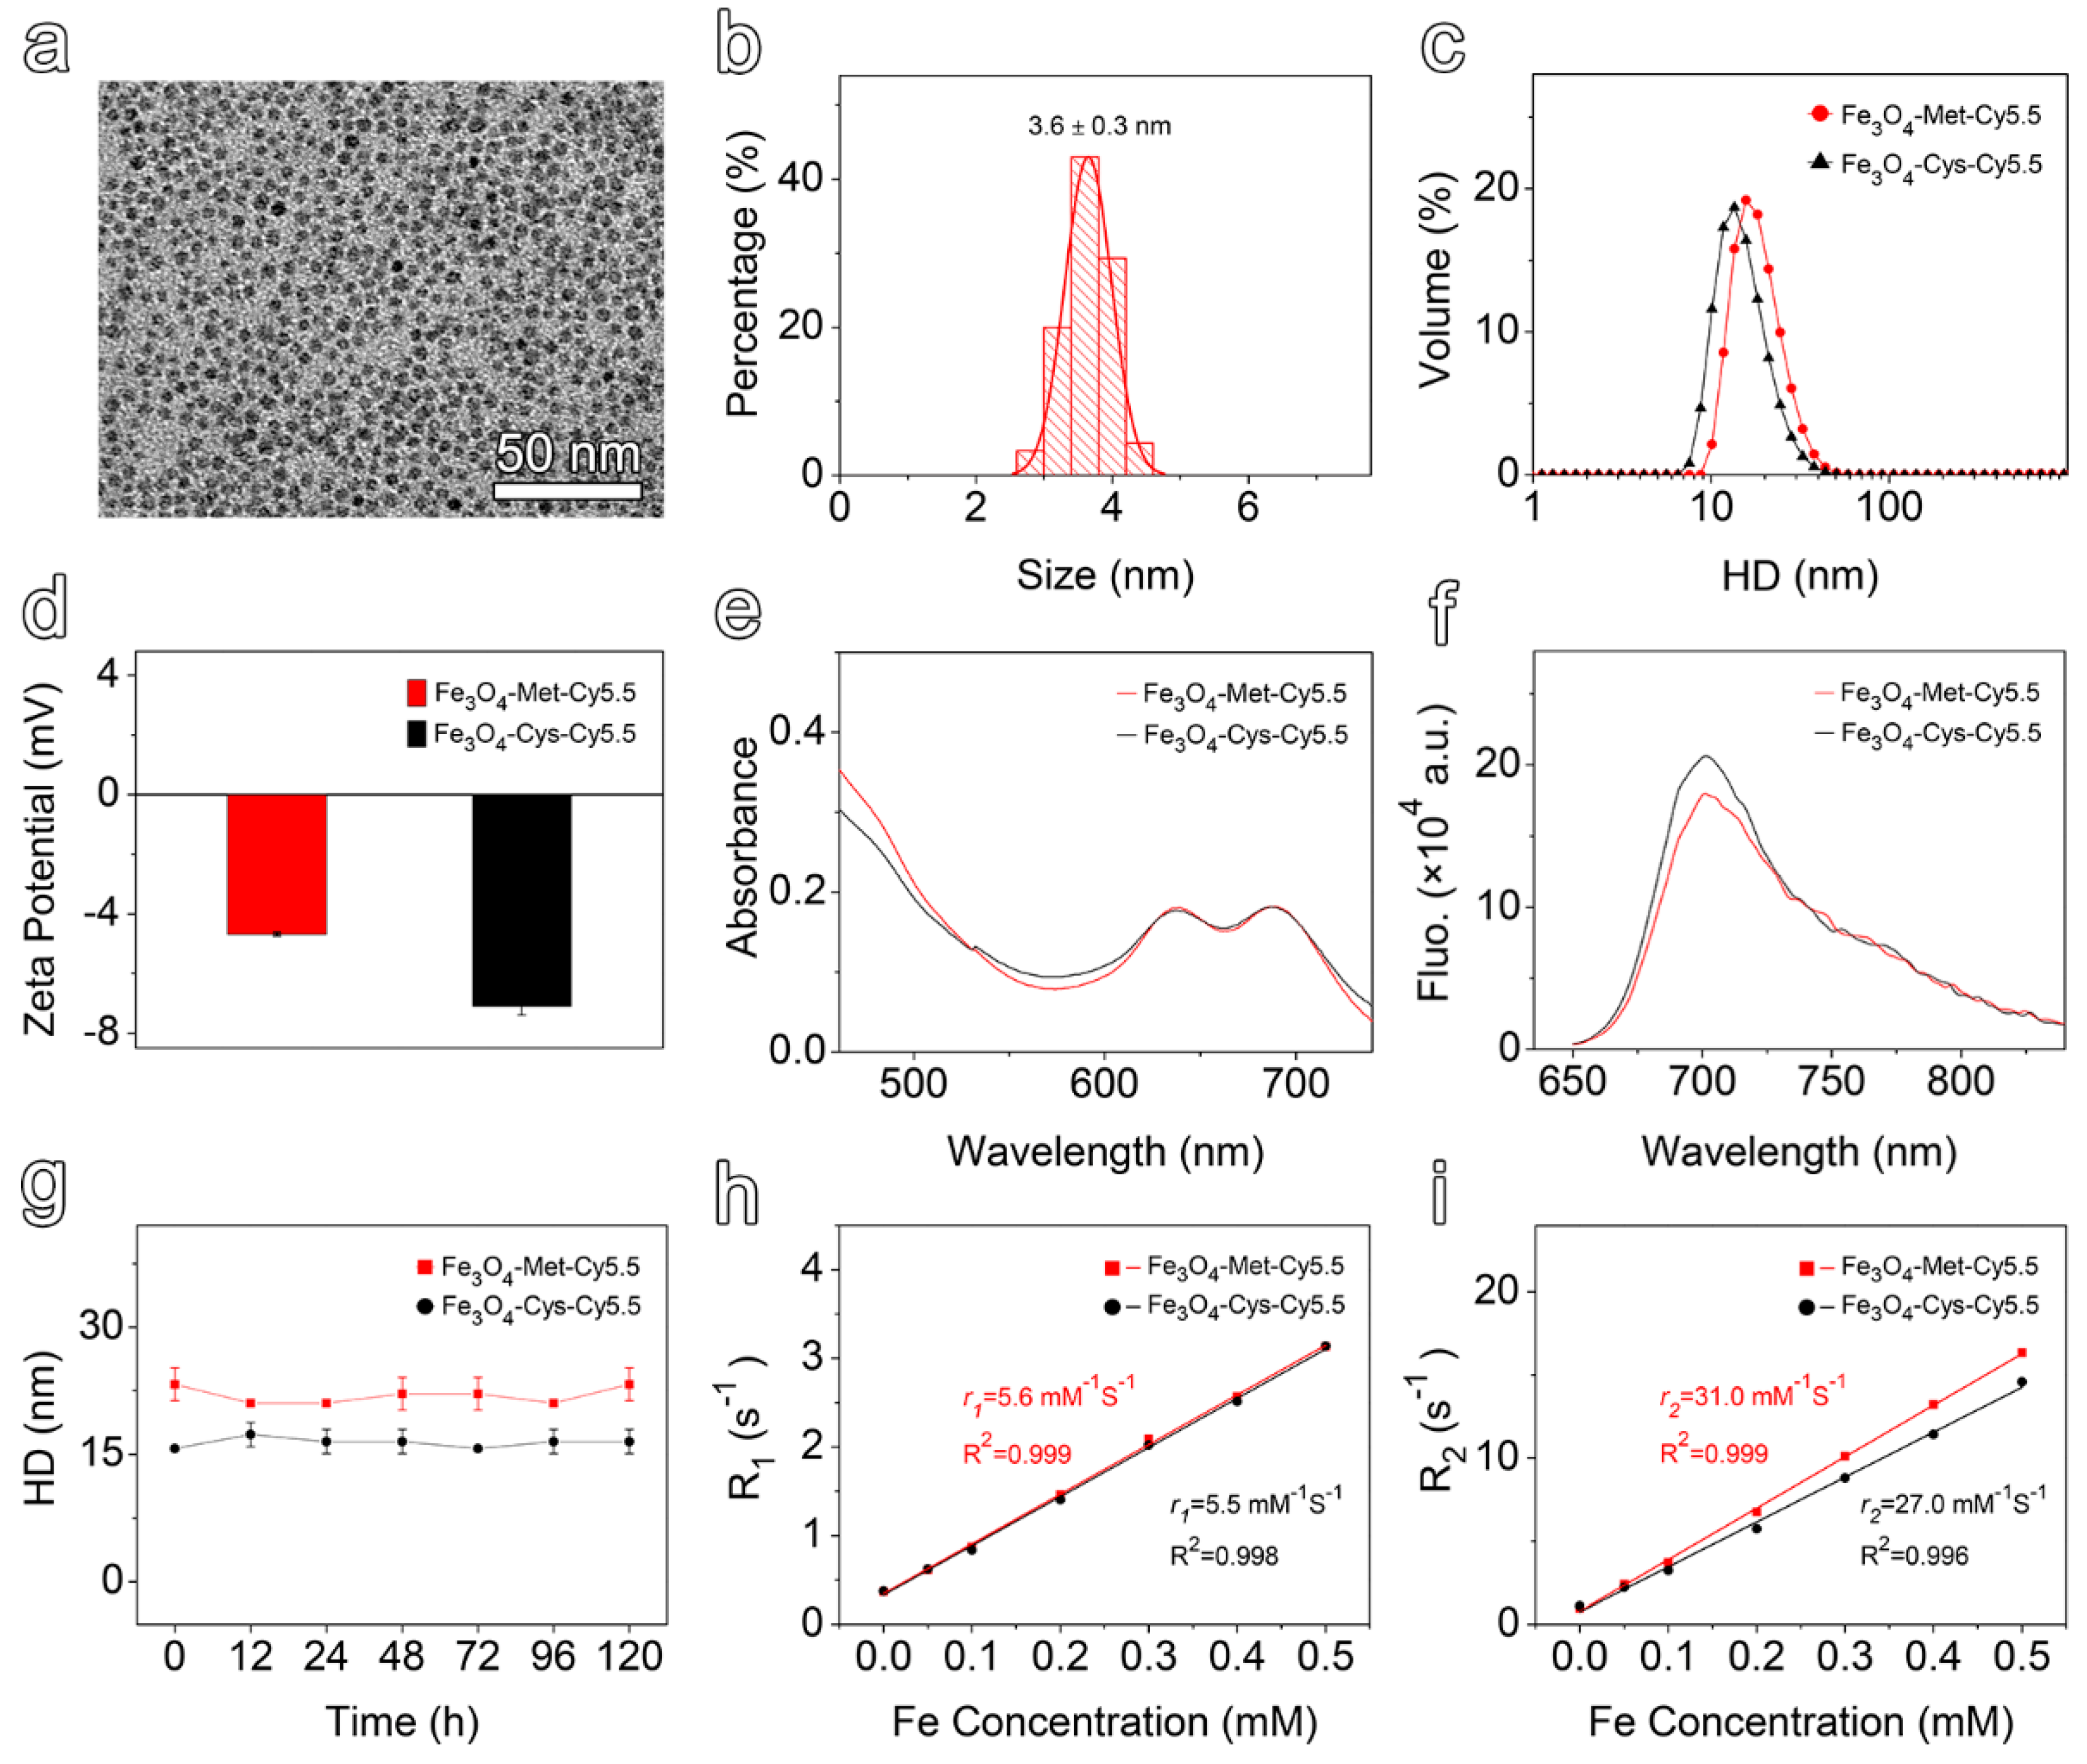

3.2. Construction and Characterization of Hypoxia-Sensitive MRI Nanoprobes